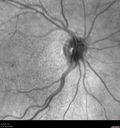

Perifoveal Microaneurysm - Not Diabetic (also reticular pseudodrusen)347 views87 year old female with fluctuating macular edema in the right eye from a perifoveal MA. (no treatment). VA 20/40 OU00000